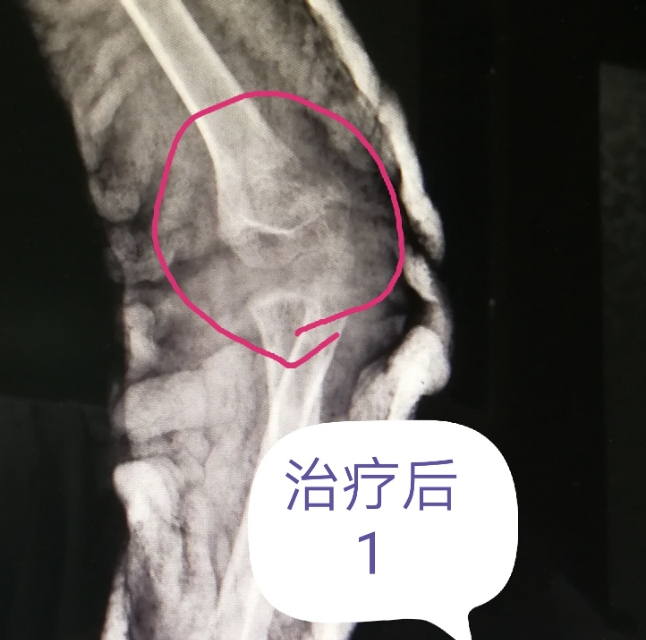

例一:肱骨髁上闭合复位,外固定。几乎解剖对位